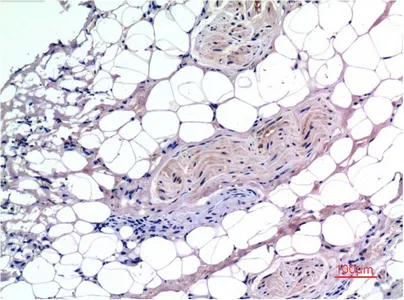

Collagen III(Q76)Mouse Monoclonal Antibody

Cat: AMM09214

Size1:50μl Price1:$118

Size2:100μl Price2:$220

Size3:500μl Price3:$980

Size2:100μl Price2:$220

Size3:500μl Price3:$980